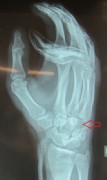

Fracture of the hamate bone

The young man (boxer) punched aggressively and once felt a sharp pain in the wrist.